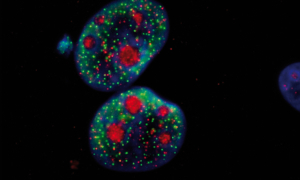

L’arrivée du numérique dans notre quotidien a révolutionné toutes nos pratiques et relations sociales. Cette technologie s’est développée à une vitesse fulgurante et est aujourd’hui indispensable. Retour en coulisses : Comment ça marche ? Quels sont ses avantages et inconvénients ? Les scientifiques bretons nous répondent. Nous retiendrons que ce qui peut être nocif, ce sont nos usages.